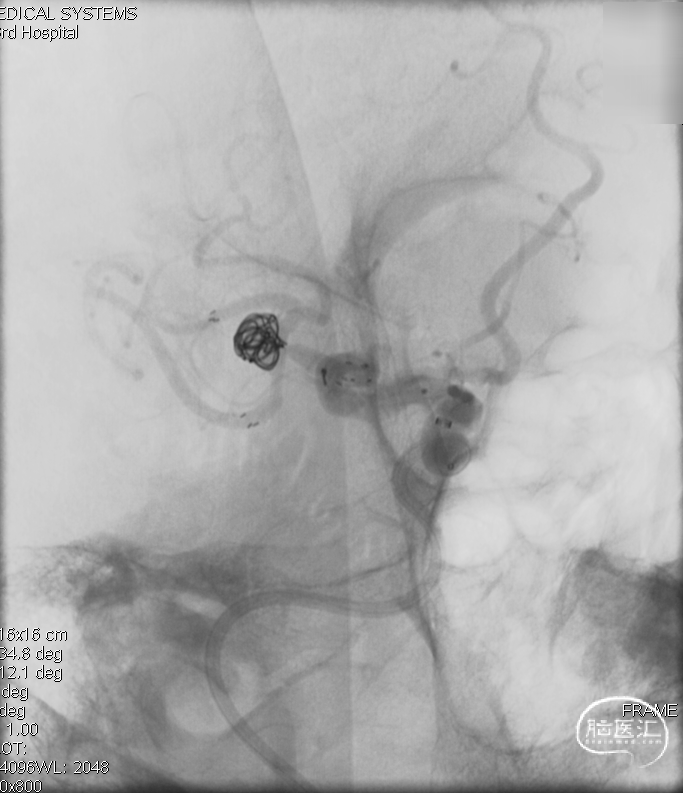

术后影像

复查标准正侧位造影, ICA、MCA、ACA主干及远端分支良好,动脉瘤栓塞满意。

术后工作位+侧位造影

术后正侧位透视

术后三维重建,支架贴壁良好,动脉瘤完全栓塞。